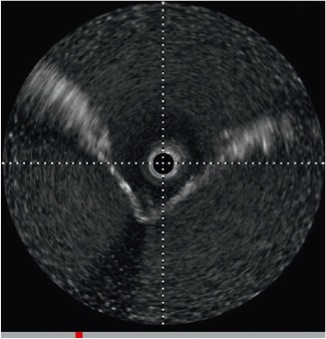

Intracardiac echocardiography (ICE) is widely used in the US, as demonstrated by the fact that approximately 50% of the experts involved in the 2007 consensus statement on AF ablation routinely used ICE to facilitate the transseptal procedure and/or to guide catheter ablation [3434. Calkins H, Brugada J, Packer DL, Cappato R, Chen SA, Crijns HJ, Damiano RJ, Jr, Davies DW, Haines DE, Haissaguerre M, Iesaka Y, Jackman W, Jais P, Kottkamp H, Kuck KH, Lindsay BD, Marchlinski FE, McCarthy PM, Mont JL, Morady F, Nademanee K, Natale A, Pappone C, Prystowsky E, Raviele A, Ruskin JN, Shemin RJ, Heart Rhythm Society, European Heart Rhythm Association, European Cardiac Arrhythmia Society, American College of Cardiology, American Heart Association, Society of Thoracic Surgeons. HRS/EHRA/ECAS expert consensus statement on catheter and surgical ablation of atrial fibrillation: recommendations for personnel, policy, procedures and follow-up - A report of the Heart Rhythm Society (HRS) Task Force on Catheter and Surgical Ablation of Atrial Fibrillation developed in partnership with the European Heart Rhythm Association (EHRA) and the European Cardiac Arrhythmia Society (ECAS); in collaboration with the American College of Cardiology (ACC), American Heart Association (AHA), and the Society of Thoracic Surgeons (STS) - Endorsed and approved by the governing bodies of the American College of Cardiology, the American Heart Association, the European Cardiac Arrhythmia Society, the European Heart Rhythm Association, the Society of Thoracic Surgeons, and the Heart Rhythm Society. Europace. 2007;9:335-79. ]. ICE does not require heavy sedation or general anaesthesia, as are commonly required in patients undergoing TOE. However, all ICE probes are currently mono-planar (with or without Doppler capabilities), while TOE is multi-planar and some also have three-dimensional capabilities. However, ICE catheters are expensive and have significant cost implication whereas TOE probes are reusable. TOE is generally thought to give better imaging during transseptal puncture and, most importantly, during the performance of the subsequent steps in structural interventions.

When using ICE imaging, tenting of the interatrial septum should be identified in the long-axis view and clear visualisation of the point of maximal tenting should be obtained before puncturing ( Figure 16 ). The relationship with the aortic root can be obtained by counter-clockwise rotation of the ICE catheter. Confirmation of the location of the ICE catheter in the LA can be obtained by injection of non-agitated saline or contrast during ICE imaging or the presence of a left-to-right shunt with colour Doppler.